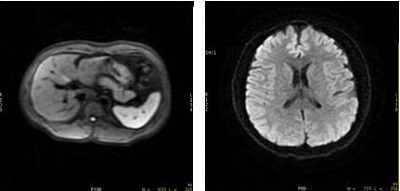

Figure 6. 3 in 1 image on left (abdomen) and Tetrahedral average image on right (head)

Figure 10. 3 in 1 image on left (abdomen) and Tetrahedral average image on right (head)